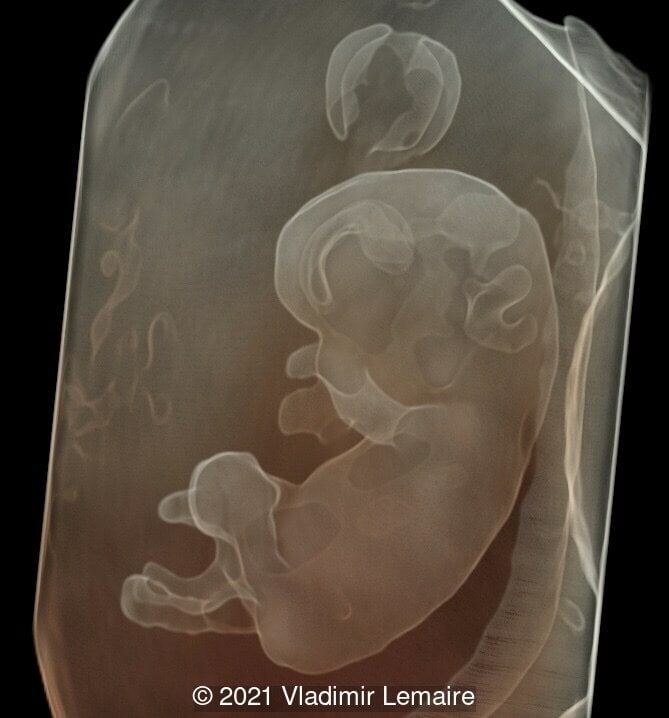

A rendered image of the same embryo in Silhouette mode.

Image 3 A rendered image of the same embryo in Silhouette mode.